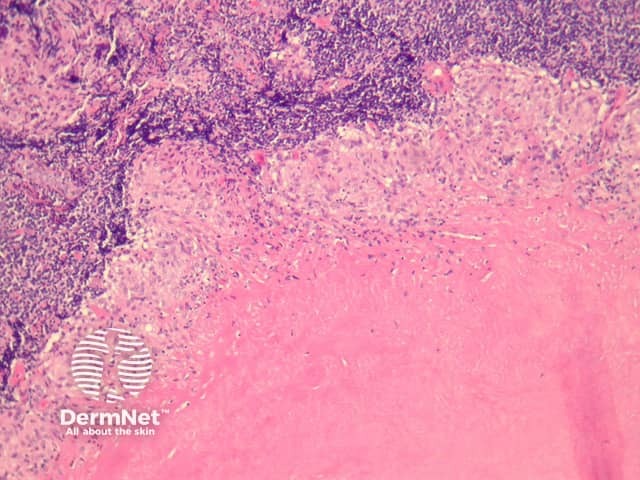

Primary inoculation with tubercle bacilli may begin with surface ulceration, epidermal hyperplasia, and a dense dermal infiltrate rich in neutrophils (figure 1). Disseminated cutaneous tuberculosis and orificial tuberculosis will typically show a similar neutrophilic reaction in early lesions. Over time, the neutrophils are replaced by chronic inflammatory cells and necrotising granulomatous inflammation surrounded by numerous lymphocytes if the patient has a competent immune system (as seen with the clinical subtype tuberculosis verrucosa). Figures 2,3,4 show the same image of the characteristic necrotising granulomatous inflammation surrounded by a lymphocytic response at progressively higher magnifications. Tubercle bacilli are usually easy to find in early suppurative lesions and difficult to identify when the granulomatous inflammation has become well developed.

Lupus vulgaris is the most common clinical type of re-infection cutaneous tuberculosis and shows well-formed granulomas surrounded by chronic inflammatory cells, and central necrosis (figures 2-4). The necrosis is usually less pronounced than the example illustrated here.

Figure 2

Figure 3

Figure 4